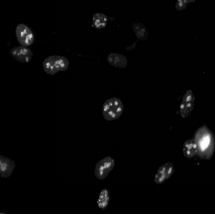

3、遺傳學(xué):用于基因表達研究和蛋白質(zhì)定位。

4、藥物篩選:用于高通量篩選實驗,評估藥物對細(xì)胞的影響。